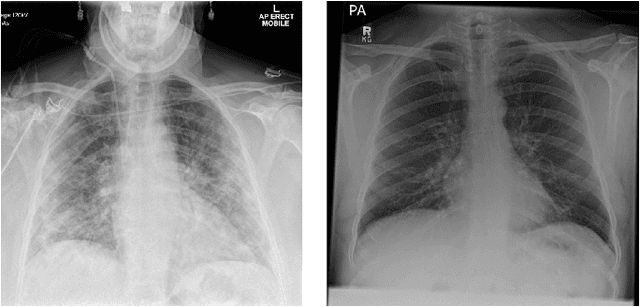

Abstract:During the COVID-19 pandemic, the sheer volume of imaging performed in an emergency setting for COVID-19 diagnosis has resulted in a wide variability of clinical CXR acquisitions. This variation is seen in the CXR projections used, image annotations added and in the inspiratory effort and degree of rotation of clinical images. The image analysis community has attempted to ease the burden on overstretched radiology departments during the pandemic by developing automated COVID-19 diagnostic algorithms, the input for which has been CXR imaging. Large publicly available CXR datasets have been leveraged to improve deep learning algorithms for COVID-19 diagnosis. Yet the variable quality of clinically-acquired CXRs within publicly available datasets could have a profound effect on algorithm performance. COVID-19 diagnosis may be inferred by an algorithm from non-anatomical features on an image such as image labels. These imaging shortcuts may be dataset-specific and limit the generalisability of AI systems. Understanding and correcting key potential biases in CXR images is therefore an essential first step prior to CXR image analysis. In this study, we propose a simple and effective step-wise approach to pre-processing a COVID-19 chest X-ray dataset to remove undesired biases. We perform ablation studies to show the impact of each individual step. The results suggest that using our proposed pipeline could increase accuracy of the baseline COVID-19 detection algorithm by up to 13%.